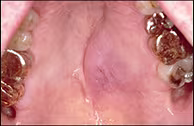

Clinical examination revealed a 2.5 x 3.0 cm raised firm nonindurated mass on the left hard palate. The epicenter of the mass was adjacent to the maxillary left first molar and the lesion extended to the midline (Figure 1). The lesion was compressible to palpation and demonstrated a slight bluish hue. The remainder of the oral cavity was within normal limits. The patient’s dentition was in good repair and several cast gold restorations were present. Radiographs of the left maxilla were negative for any pathology and all teeth in the area tested vital.

Figure 1. Smooth-surfaced raised lesion of left hard palate.